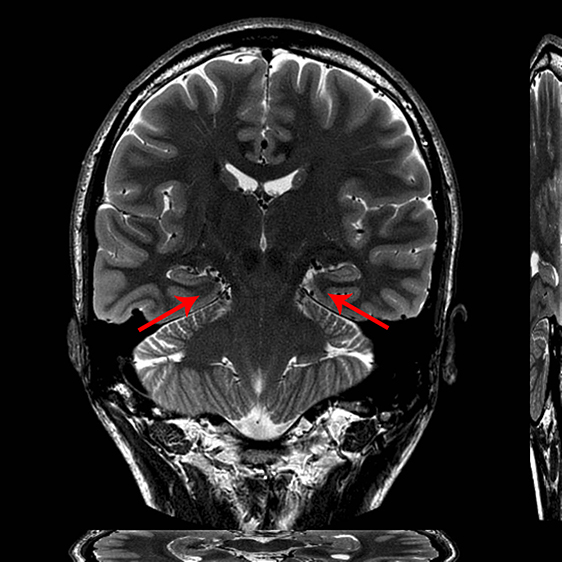

Brain image.

Edvard Moser and May-Britt Moser were awarded the Nobel Prize for their discovery of a new type of nerve cells – grid cells – that create a form of internal coordinate system. The picture comes from a magnetic image of the brain and indicates where in the brain the grid cells are located.

Photo: Lars Nyberg